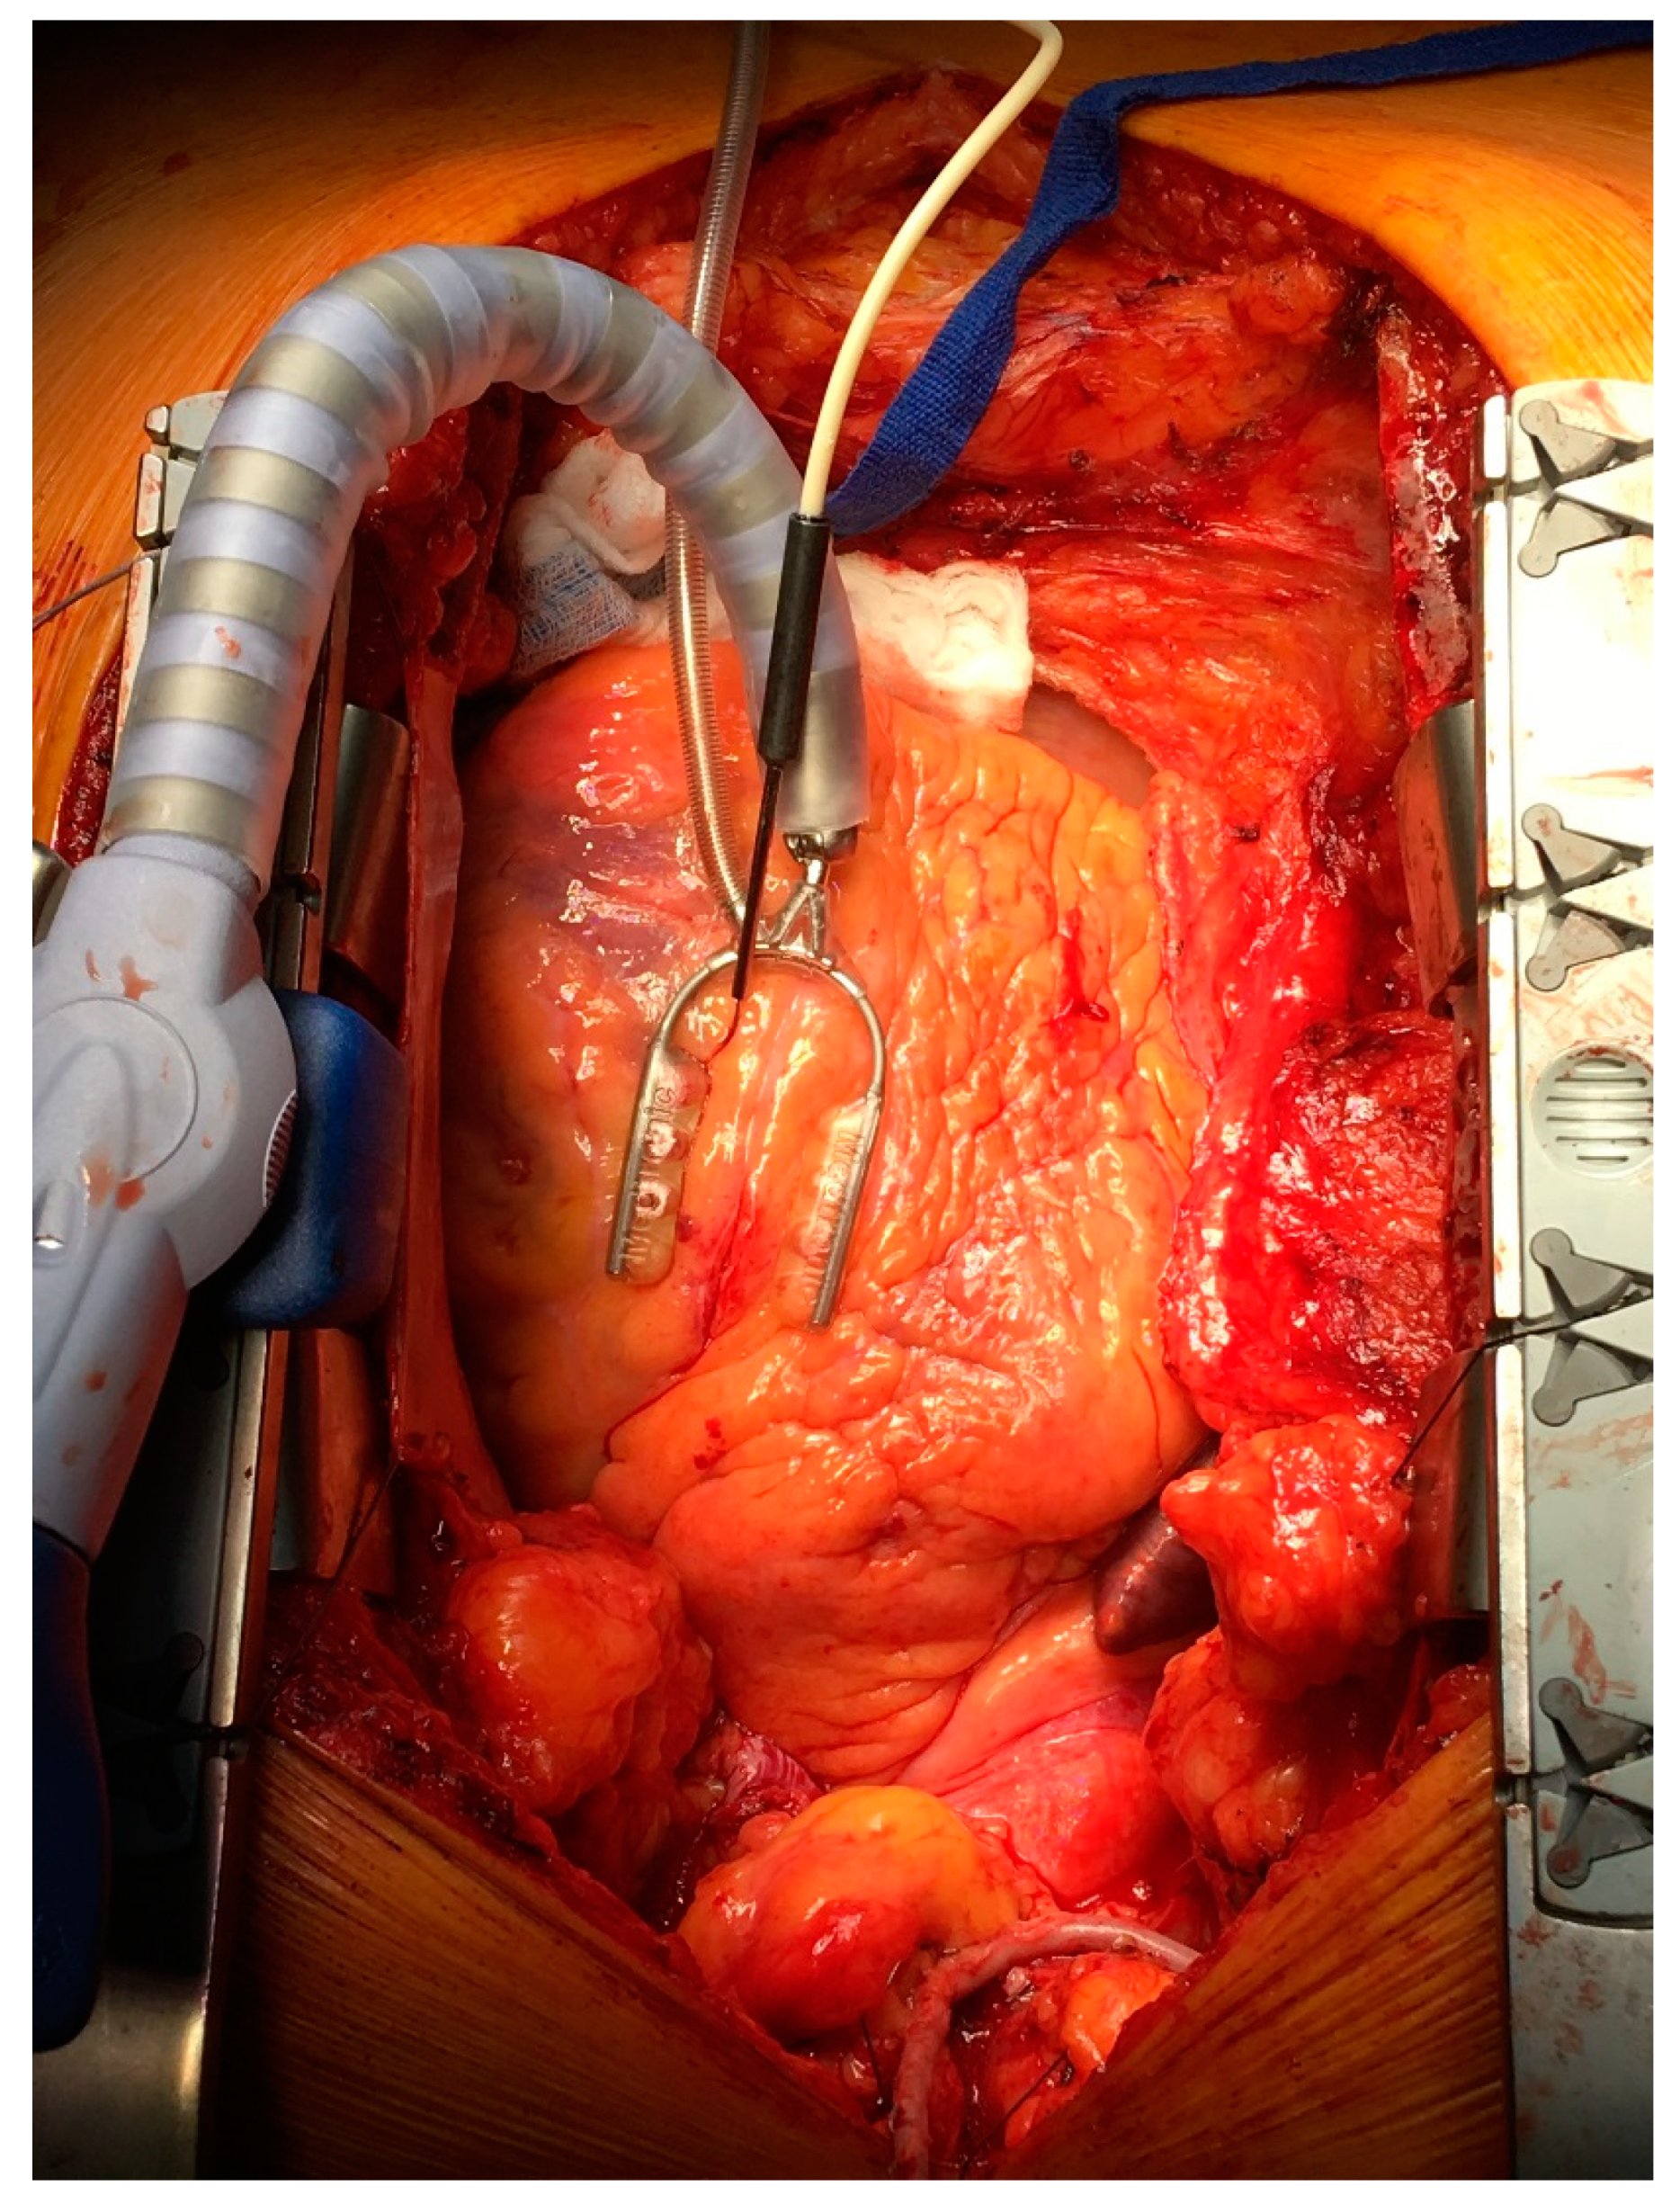

All measurements of myocardial microvascular perfusion were carried out using laser Doppler flowmetry (Periflux System 5000, Perimed, Järfälla, Sweden) equipped with the special insertion probe (Stainless Steel Probe 411-311, Perimed, Järfälla, Sweden). Laser Doppler intramuscular fiber-optic perfusion probe (Figure 1) was inserted 3–5 mm into the myocardium during beating heart surgery downstream from the planned anastomosis (Figure 2). After clamping and incision of coronary artery, an anastomosis was performed with prepared graft. When anastomosis was completed, clamps were taken off and the flow through the coronary artery was restored. All measurements were carried out continuously during the operation. Baseline registration was performed for approximately 3 min. Then, the perfusion measurements were continued during vascular anastomosis and approximately 3 min after occlusion release. At the end, the needle probe was removed from the myocardium and subsequently the next anastomosis was performed.

Figure 2. Laser Doppler intramuscular fiber-optic perfusion probe was inserted into the myocardium during beating heart surgery downstream from the planned anastomosis.